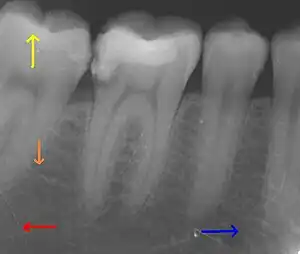

This X-ray film depicts some of the teeth in the lower right quadrant. The arrows point in the following directions: distal , mesial , coronal , apical .